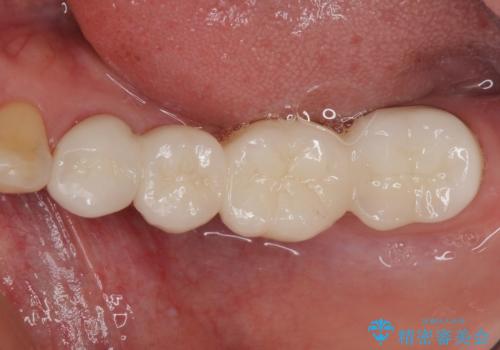

治療開始の日に欠損部も含めて仮歯が装着され、今までの不具合や不快感があっという間に改善されました。

抜歯部位の治癒を待つために時間がかかりましたが、来院回数は数回で済み、患者様には大変満足していただきました。